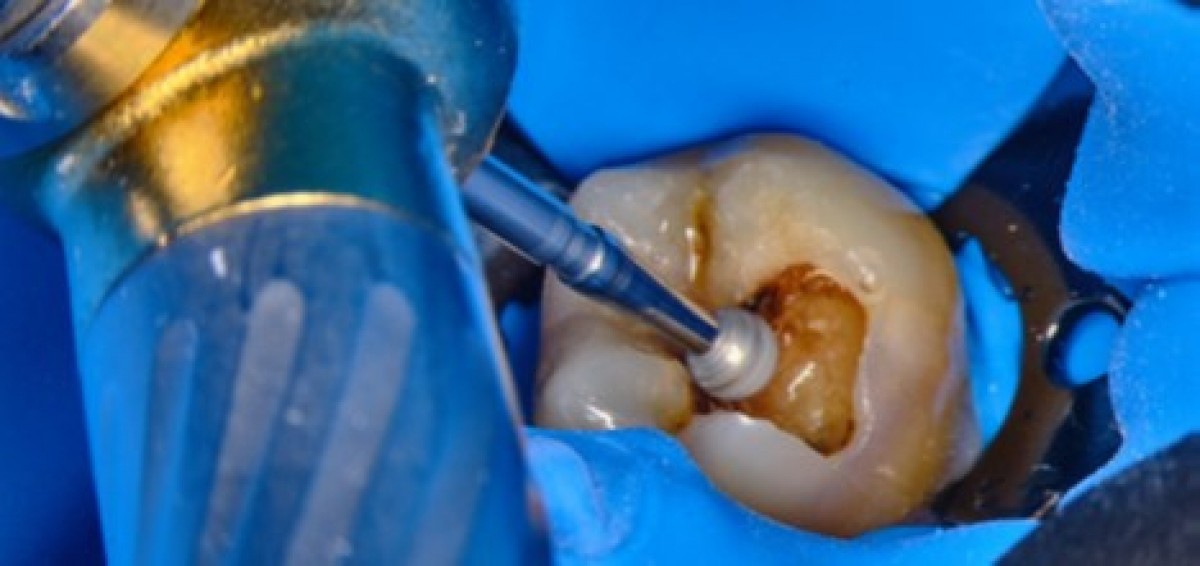

Rubber dam was placed on the tooth in order to isolate the operative field 3 (Fig. 2) and the root canal treatment was began. The first step of a correct shaping of the root canal system is the access cavity 4: it ideally has to be the coronal projection of the root canals and it is meant to be as small as practical. The coronal composite was carefully removed with a diamond-coated bur as soon as the pulp chamber floor was reached (Fig. 3). After designing the access cavity, the carboxy cement that had been placed in the root canals in the primary treatment was removed, and the root canal openings were sought and found with the help of the operative microscope (Fig. 4). Subsequently, it was managed to remove the cement from the root canals. Since the primary treatment had not respected the basic principles of shaping, cleaning and filling tridimensionally the root canal system, it was necessary to consider as the pulp was still present in the root canals. The scouting phase was executed, first with thin stainless steel manual instruments and NiTi rotary files (Fig. 5), then NiTi reciprocating files were used to shape the root canal system 5 (Fig. 6).

A 56 years-old patient came to our office complaining of an intense pain on tooth 3.8. The elements how next ended carious lesion (Fig. 15) and the x-rays confirmed that the decay was in proximity to the pulp chamber (Fig. 16). A lower alveolar nerve block was executed, then rubber dam was placed and the decay was removed with the help of a microscope (Fig. 17-19). After removing all the decayed tissue, the access cavity was completed trying to be extremely conservative and the root canal openings were found and enlarged with the help of ultrasonic tips (Fig. 20). The scouting of the root canal was executed with thin hand files (Fig. 21, 22), then the shaping procedure was carried out by means of reciprocating NiTi files (Fig. 23, 24) 9. The irrigation phase was executed with IrriFlex, a novel polypropylene irrigation tip that has a 2-side vented exits (Fig. 25-27), then the irrigant activation was done with sonic tips. Shaping and irrigation were alternated until the root canals were looking clean and appropriately tapered (Fig. 28-32) 10, 11. Paper cones were then used to dry the root canals (Fig. 33, 34) then, in this case, the obturation was done with single cone and bioceramic sealer (Fig. 35, 36). The access cavity was sealed with composite material, then an indirect restoration was booked.